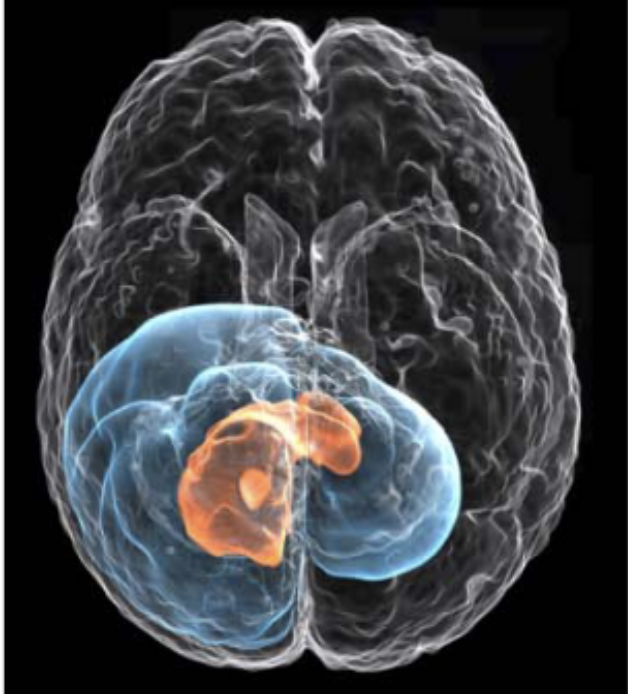

Learn-Morph-Infer: a new way of solving the inverse problem for brain tumor modelingIvan Ezhov, Kevin Scibilia, Katharina Franitza, Felix Steinbauer, Suprosanna Shit, Lucas Zimmer, Jana Lipkova, Florian Kofler, Johannes C Paetzold, Luca Canalini, and othersMedical Image Analysis[ bibtex | html | abstract ]@article{ezhov2023learn, title = {Learn-Morph-Infer: a new way of solving the inverse problem for brain tumor modeling}, author = {Ezhov, Ivan and Scibilia, Kevin and Franitza, Katharina and Steinbauer, Felix and Shit, Suprosanna and Zimmer, Lucas and Lipkova, Jana and Kofler, Florian and Paetzold, Johannes C and Canalini, Luca and others}, journal = {Medical Image Analysis}, volume = {83}, pages = {102672}, year = {2023}, publisher = {Elsevier}, html = {https://www.sciencedirect.com/science/article/pii/S1361841522003000}, abbr = {ezhov2023learn.png} }Current treatment planning of patients diagnosed with a brain tumor, such as glioma, could significantly benefit by accessing the spatial distribution of tumor cell concentration. Existing diagnostic modalities, e.g. magnetic resonance imaging (MRI), contrast sufficiently well areas of high cell density. In gliomas, however, they do not portray areas of low cell concentration, which can often serve as a source for the secondary appearance of the tumor after treatment. To estimate tumor cell densities beyond the visible boundaries of the lesion,numerical simulations of tumor growth could complement imaging information by providing estimates of full spatial distributions of tumor cells. Over recent years a corpus of literature on medical image-based tumor modeling was published. It includes different mathematical formalisms describing the forward tumor growth model. Alongside, various parametric inference schemes were developed to perform an efficient tumor model personalization, i.e. solving the inverse problem. However, the unifying drawback of all existing approaches is the time complexity of the model personalization which prohibits a potential integration of the modeling into clinical settings. In this work, we introduce a deep learning based methodology for inferring the patient-specific spatial distribution of brain tumors from T1Gd and FLAIR MRI medical scans. Coined as Learn-Morph-Infer, the method achieves real-time performance in the order of minutes on widely available hardware and the compute time is stable across tumor models of different complexity, such as reaction–diffusion and reaction– advection–diffusion models. We believe the proposed inverse solution approach not only bridges the way for clinical translation of brain tumor personalization but can also be adopted to other scientific and engineering domains.

Modelling glioma progression, mass effect and intracranial pressure in patient anatomyJana Lipková, Bjoern Menze, Benedikt Wiestler, Petros Koumoutsakos, and John S LowengrubJournal of the Royal Society Interface[ bibtex | software | html | abstract ]@article{lipkova2022modelling, title = {Modelling glioma progression, mass effect and intracranial pressure in patient anatomy}, author = {Lipkov{\'a}, Jana and Menze, Bjoern and Wiestler, Benedikt and Koumoutsakos, Petros and Lowengrub, John S}, journal = {Journal of the Royal Society Interface}, volume = {19}, number = {188}, pages = {20210922}, year = {2022}, publisher = {The Royal Society}, html = {https://doi-org.ezp-prod1.hul.harvard.edu/10.1098/rsif.2021.0922}, software = {https://github.com/JanaLipkova/GliomaSolver}, abbr = {lipkova2022modelling.png} }Increased intracranial pressure is the source of most critical symptoms in patients with glioma, and often the main cause of death. Clinical interventions could benefit from non-invasive estimates of the pressure distribution in the patient’s parenchyma provided by computational models. However, existing glioma models do not simulate the pressure distribution and they rely on a large number of model parameters, which complicates their calibration from available patient data. Here we present a novel model for glioma growth, pressure distribution and corresponding brain deformation. The distinct feature of our approach is that the pressure is directly derived from tumour dynamics and patient-specific anatomy, providing non-invasive insights into the patient’s state. The model predictions allow estimation of critical conditions such as intracranial hypertension, brain midline shift or neurological and cognitive impairments. A diffuse-domain formalism is employed to allow for efficient numerical implementation of the model in the patient-specific brain anatomy. The model is tested on synthetic and clinical cases. To facilitate clinical deployment, a high-performance computing implementation of the model has been publicly released.